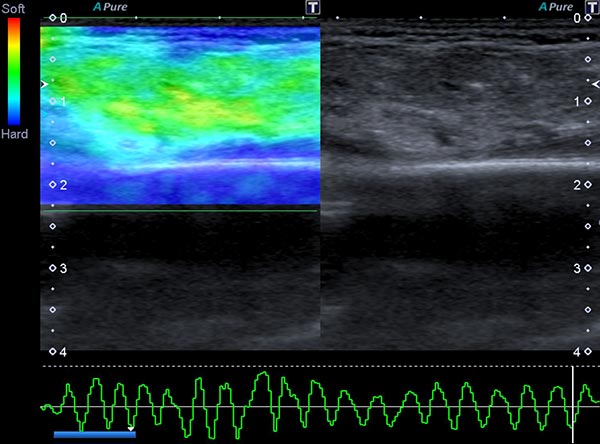

In ultrasound elastography, the mechanical stiffness of the tumor can be color-coded (left image), with the corresponding B-scan on the right. In color coding, hard tissue is shown in blue, medium-hard tissue in green and soft tissue in red. The tumor itself is medium-hard to slightly softer (green) than the surrounding tissue (blue).